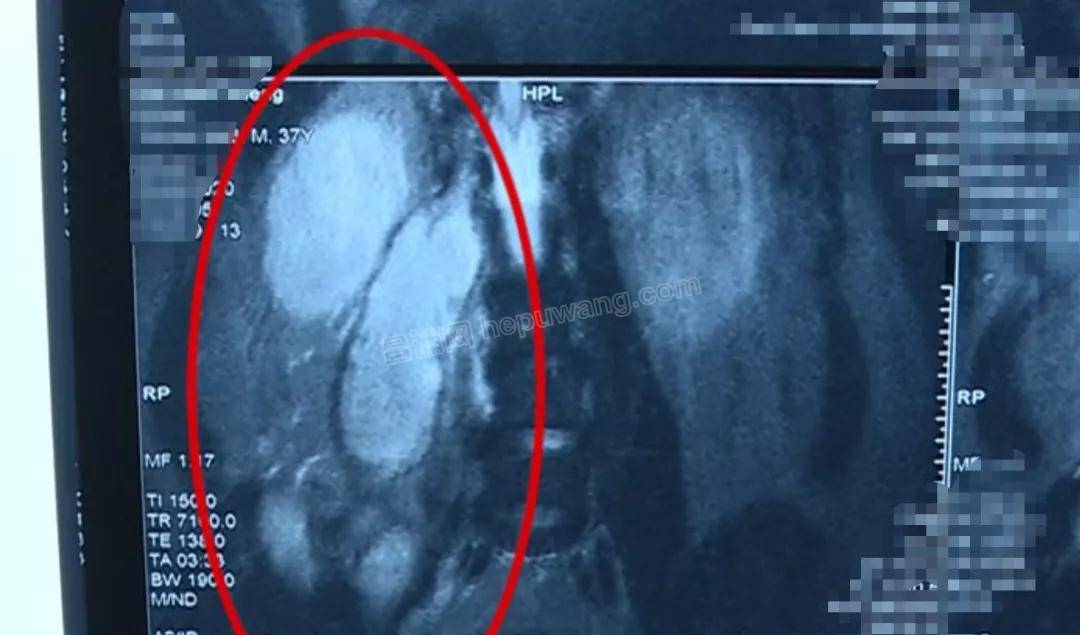

王主任认为

脓肿大部分来源于腹膜后

由于患者体温不稳定

腰腿疼痛没有好转

医护人员决定为其进行手术

微信图片_20200604111836.jpg